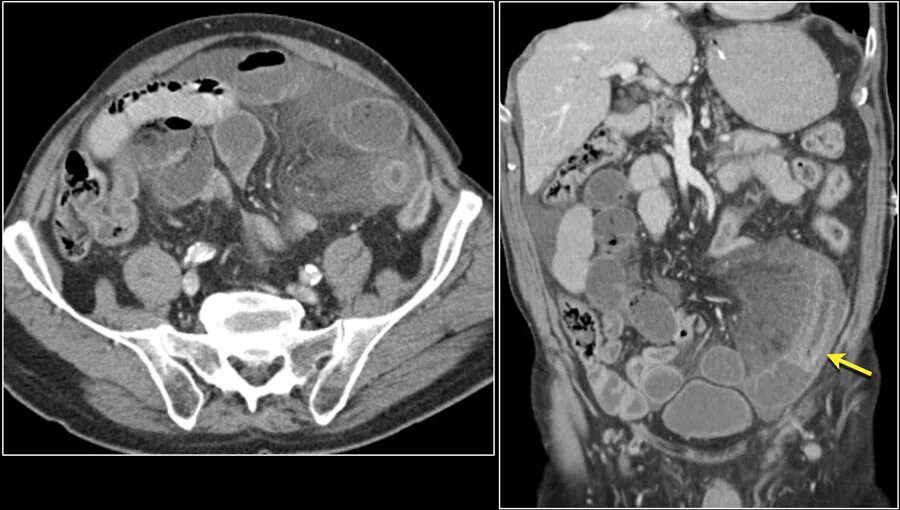

Асцит в малом тазу